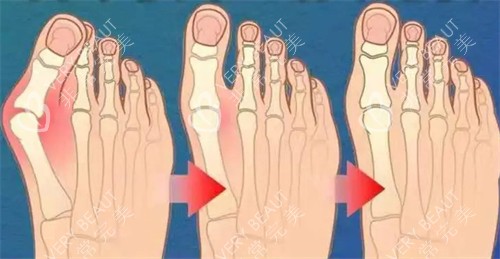

拇外翻矫正手术

拇外翻,俗称大脚骨,是更常见的足部问题之一。苏敬达医生针对拇外翻的矫正手术,根据病情轻重分为三档:

轻度拇外翻矫正手术:费用从16800元起。轻度患者,拇趾外翻角度较小,手术难度相对较低,改善也更快。

中度拇外翻矫正手术:费用从19800元起。中度患者,拇趾外翻角度较大,需要更精细的手术操作和更长的改善期。

重度拇外翻矫正手术:费用从22800元起。重度患者,拇趾外翻严峻,可能伴有其他足部问题,手术复杂度和风险相应增加。